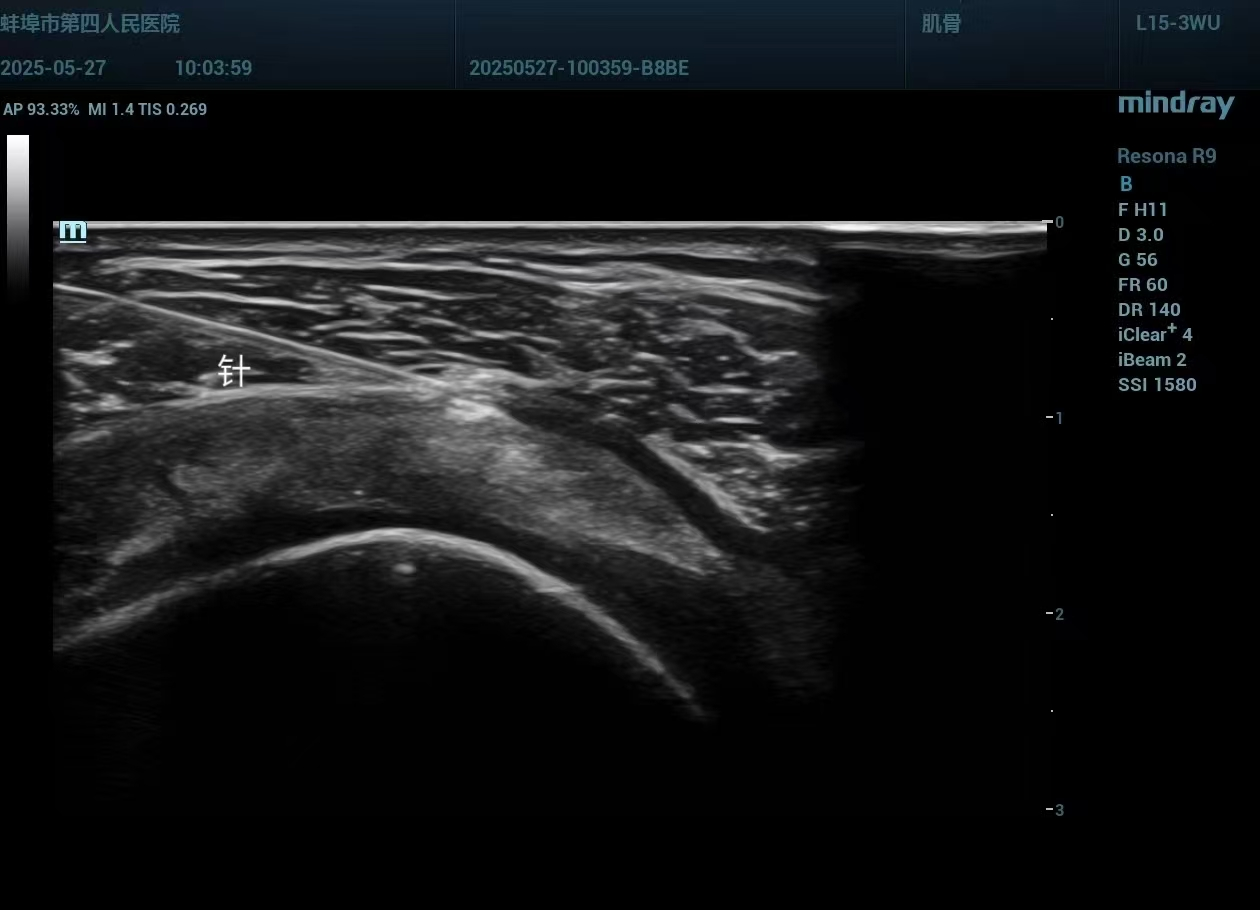

超声引导下肌骨介入治疗,是将超声的“可视化”优势与介入治疗的“精准性”完美结合的先进技术。治疗时,医生可通过超声实时动态监测,清晰定位滑囊、关节腔、腱鞘、周围神经等病变部位,精准锁定治疗靶点;同时避开大血管、神经等重要结构,选择最安全的穿刺路径,在可视状态下完成局部药物注射等治疗操作。

相较于传统触诊引导的注射治疗,它实现了从“盲操作”到“精准治”的跨越,不仅创伤极小、术后体表无瘢痕,更兼具安全性高、恢复快速、疗效确切的突出优势,让治疗更有底气、更放心。